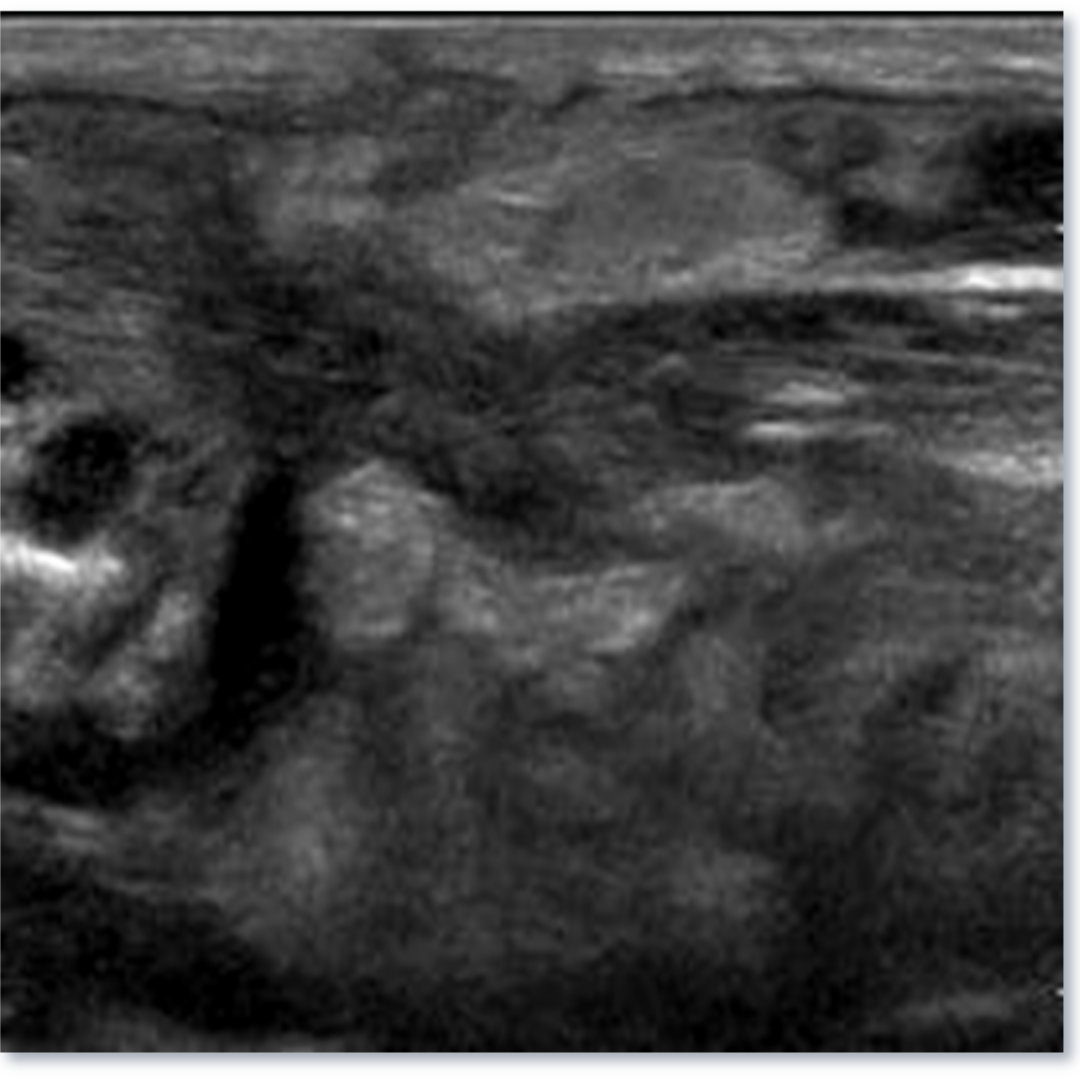

ASPECTO DEL LECHO TIROIDEO A 4 SEMANAS

Figura 1. Corte longitudinal del lecho tiroideo, cambios post quirúrgicos normales recientes en el lecho tiroideo donde se observa un aumento de ecogenicidad de hipodermis, engrosamiento dérmico, cambios a nivel profundo con dificultad para observar planos debido al edema.